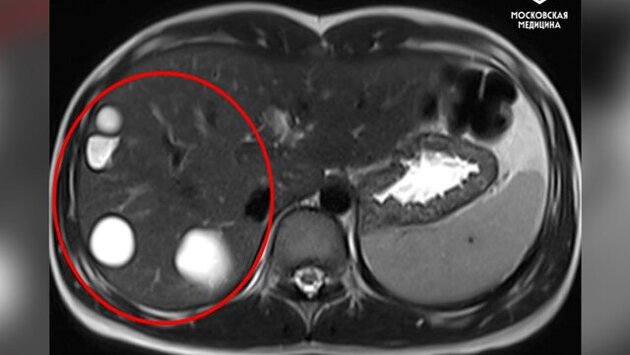

В рамках операции врачи, используя лапароскопию, удалили из печени девочки пять паразитарных кист. Пациентку выписали спустя 5 дней.